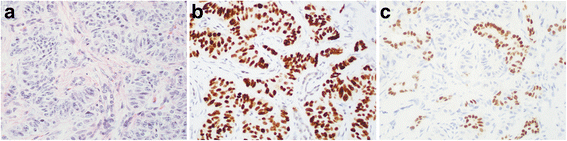

结果解读:IHC结果显示,NKX2.2、PDX-1、CDX-2的表达具有部位特异性——GI和胰腺NET中,NKX2.2阳性率为84%(n=98),PDX-1为14%(n=98),CDX-2为53%(n=98);肺NET中,三者均为阴性(n=11);PTF1A在所有NET和正常组织中均呈阳性(提示其为“泛神经内分泌标志物”,无部位特异性)。为验证TMA结果的可靠性,作者对8例GI和胰腺NET的全组织切片重复IHC,结果与TMA完全一致(弥漫阳性或完全阴性),排除了TMA“取样偏差”的影响。

(图2:不同部位NET的IHC结果示例——十二指肠NET中NKX2.2弥漫阳性,胃NET中NKX2.2阴性;阑尾NET中PDX-1阳性,结肠NET中PDX-1阴性)